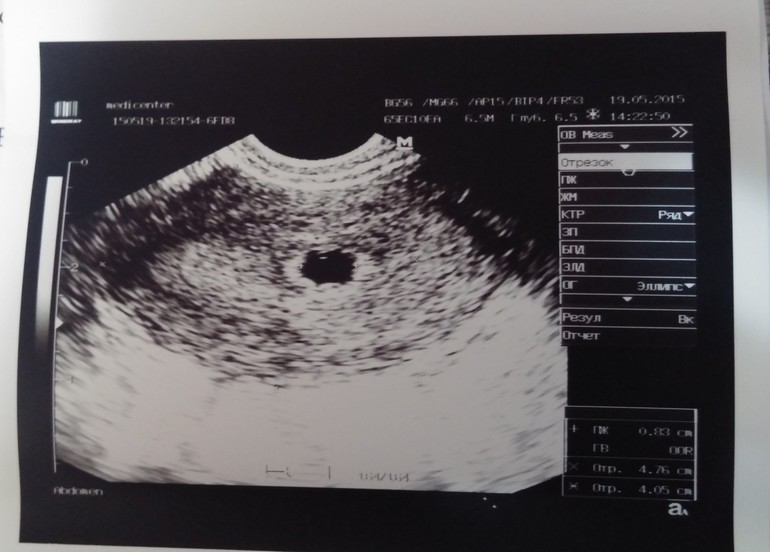

ФолликулометрияИ так=) нас нашли!!!))) ура!!!!😍😍😍по месячным срок 6нед2дня. По результатам узи-4 недельки) сказали придти недельки через 2 на сб. Есть в пя киста жт 20мм. На счет прогестерона сказала что все нормально. Он на этой недельке должен физиологически понижаться. Потом опять повышается. Вот мы))бусеныш мой💏👣